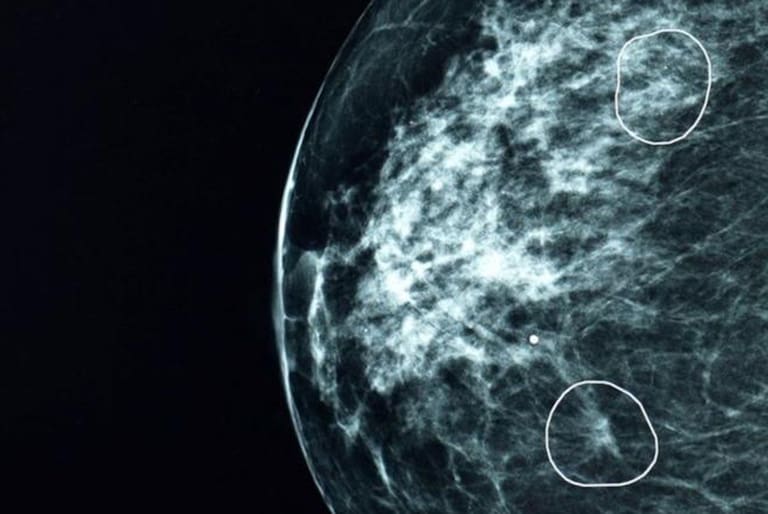

The AI tool Mia, used in a UK NHS trial, analyzed over 10,000 mammograms and detected early-stage breast cancers in 11 women that human doctors missed. This early detection enabled less invasive treatment and improved patient outcomes, demonstrating AI's significant role in preventing harm through enhanced medical diagnosis.[AI generated]